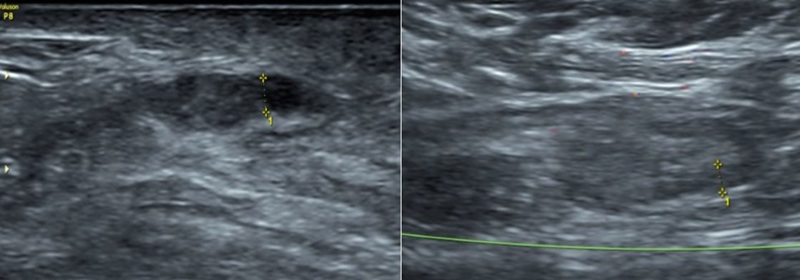

Kết quả siêu âm tuyến vú phát hiện đám giảm âm kèm giãn ống tuyến vú phải, được phân loại BIRADS 4 – mức độ nghi ngờ tổn thương ác tính. Chụp X-quang tuyến vú ghi nhận nốt vôi hóa tập trung thành đám tại vú phải, phân loại BIRADS 4B.

Hình ảnh siêu âm tuyến vú phát hiện đám giảm âm kèm giãn ống tuyến vú phải